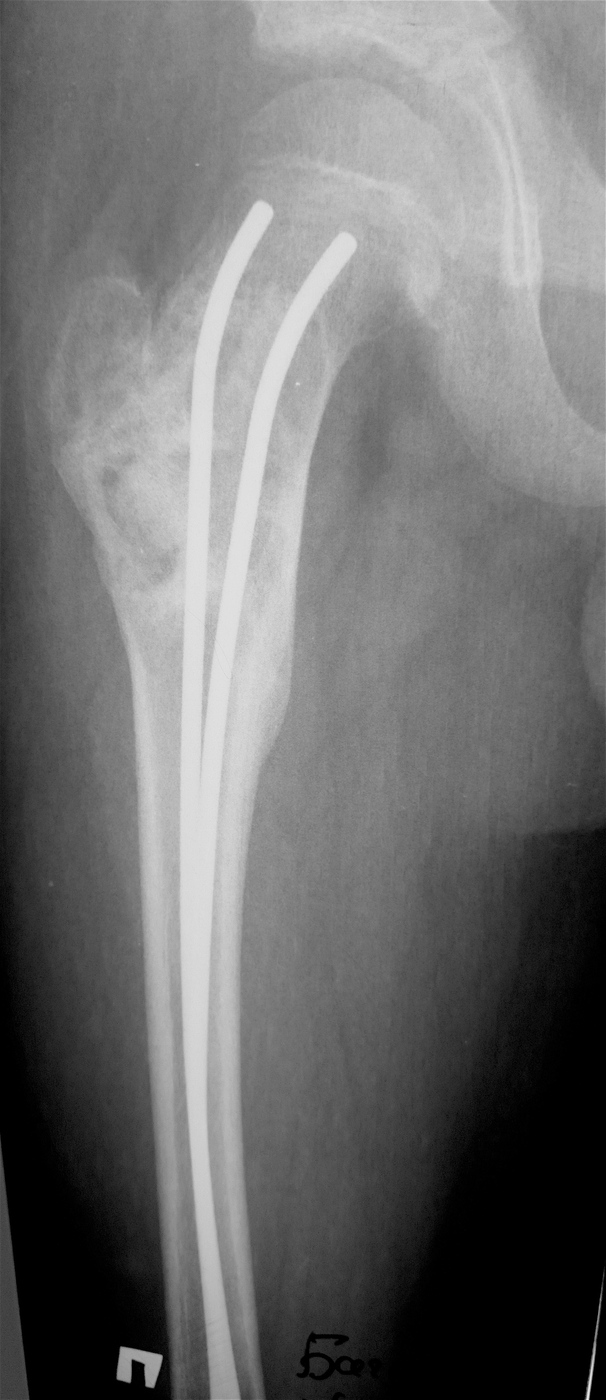

Закрытый, паталогический перелом в подвертельной области правой бедренной кости со смещением, на фоне аневризмальной костной кисты.

Выполнена резекция с аллопластикой губчатыми и кортикальными биоимплантатами "Лиопласт".